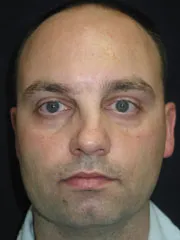

Cheek Implants, Rhinoplasty, Mandibular Advancement, Genioplasty

|

|

|

before |

after |

|

|

|

before |

after |